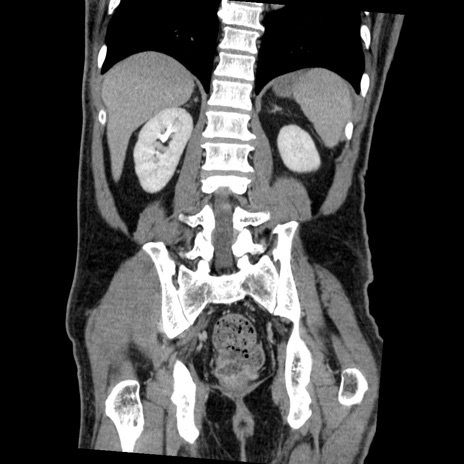

症例22(冠状断像)

【症例】50歳代男性

【主訴】腹痛

【現病歴】AVMからの被殻出血のため回復期リハ病棟入院中。 本日午後3時頃急に下腹部痛が出現した。

【既往歴】AVM、被殻出血、虫垂炎、高血圧

【身体所見】意識晴明、左半身不全麻痺、会話の理解は良好、36.5°C、腹部:膨隆、全体に板状硬、下腹部正中に圧痛点あり、反跳痛-、筋性防御不明、右下腹部にope scar

【データ】WBC 9400、CRP 0.06